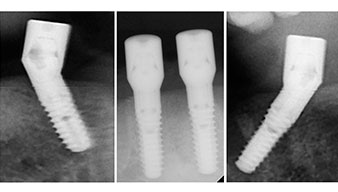

A three-dimensional cone beam computed tomography scan (CBCT, Planmeca) was performed to aid planning and minimize risks. This revealed that the quality and quantity of the available bone were sufficient for the surgery and immediate restoration using the Fast & Fixed method. Following the protocol for this concept, the implants are inserted at 35, 32, 42 and 45. Angling the distal implants by up to 45° shifts the emergence profile to posterior and generates a larger support polygon (Fig. 3).

This corresponds to the next preset position in the Implantmed. Here we see the W&H contra-angle handpiece being held at a 45° angle to mesiocaudal in the region of 45 in order to preserve the mental nerve. The mental foramen is used as the anatomic reference for all drilling in this region. The subsequent holes were drilled at a reduced speed of 300 rpm (Fig. 10 and 11).

The next programmed setting is already for placement of the implants. In our practice we usually employ a torque of 32 Ncm to place the implants (Fig. 12 and 13).

High primary stability is an absolute requirement for an immediate restoration. In order to achieve this, the hole was not tapped in this case. The W&H Implantmed drill unit used here is equipped with a suitable special mode for this, which can also be directly selected and is indispensable for many indications. The final revolutions when placing the implants exceeded the value of 32 Ncm and were performed by hand. In such cases, we recommend utilizing the implants’ self-tapping function and twisting the implants backwards and forwards several times. This allows the implant to approach the final position gradually without exerting excessive pressure on the bone (Fig. 14).

The light increases the contrast in the oral cavity and improves visual perception. Both the contra-angle handpiece and the S-11 straight handpiece from W&H are externally cooled, which can be seen as a great advantage because the saline solution arrives exactly where it’s needed and can also be subsequently adjusted if necessary. The contra-angle and straight handpieces can be dismantled, which is highly recommended for hygiene and sterilizability. Four SKY implants measuring 4.0 x 14mm were placed.